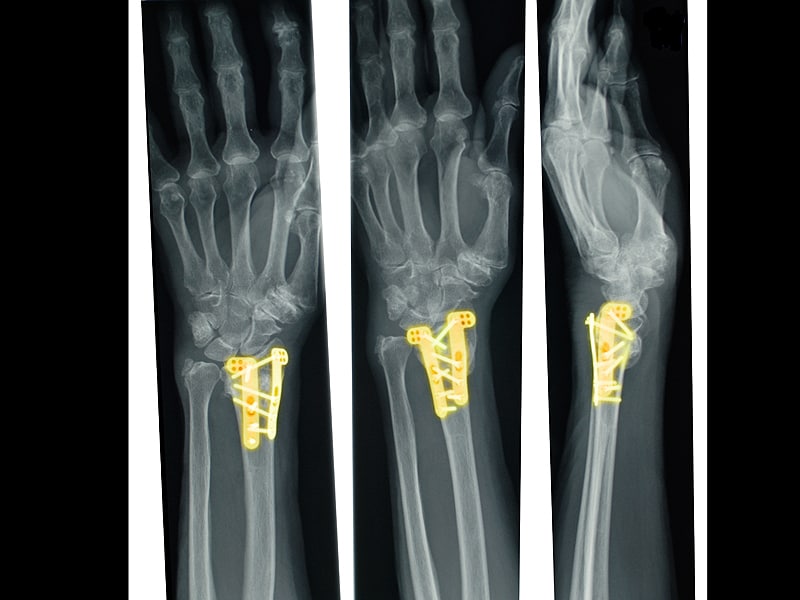

Plain radiographs of the left wrist following operative fixation. a

Plain radiographs of the left wrist following operative fixation. a Metal Plate In Wrist Causing Pain The break was in the first metatarsal, and i had surgery to stabilize it with 2 screws and a titanium plate. Removal of the metal may be what’s needed to treat the irritation. The metal elements in some implant products can cause irritation to the nearby tissues. It is a common condition that affects 10% to 15% of the population.. Metal Plate In Wrist Causing Pain.